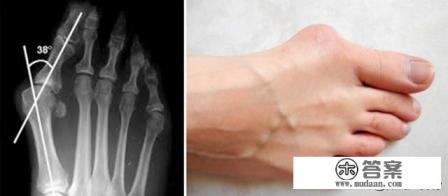

1、我们把拇趾偏斜角度小于15度的叫生理性拇外翻,就是正常人几乎都有,拇趾偏斜角度超过15度叫病理性拇外翻,病理性拇外翻无疑问肯定是要治疗的,那生理拇外翻我们是有争议的。

可以及时去骨科,看医生面谈,进行初步的医学检查,并对足部进行常规的x光检查,以确定骨骼畸形的程度。对于比较严重的大脚骨,可以选择截骨矫形手术治疗,费用一般需要2万元左右。主要包括手术费、麻醉费、以及床费,需要1万元左右,另外是截骨后,线内固定钢板螺钉,费用需要8万元左右。